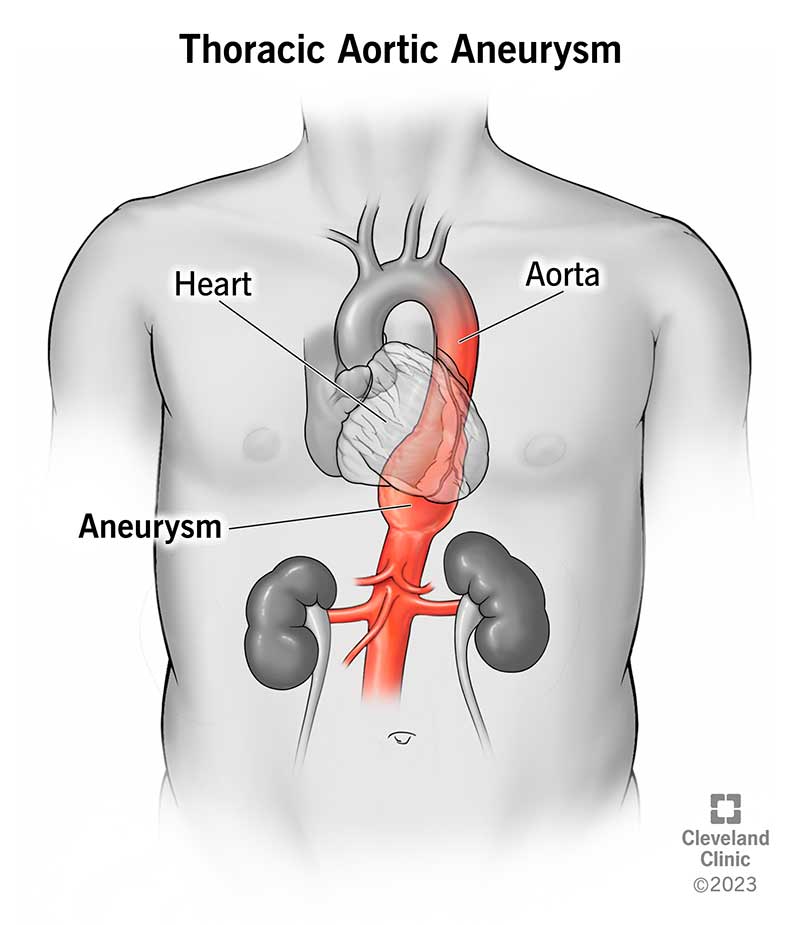

Aortic Aneurysm LaytinPride

Aortic Aneurysm LaytinPride

ANEURYSM

ANEURYSM

Thoracic Aortic Aneurysm Symptoms Treatment